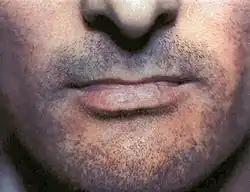

Lichen planus (LP) is a chronic inflammatory and autoimmune disease that affects the skin, nails, hair, and mucous membranes.[1][2] It is not an actual lichen, but is named for its appearance.[3] It is characterized by polygonal, flat-topped, violaceous papules and plaques with overlying, reticulated, fine white scale (Wickham's striae), commonly affecting dorsal hands, flexural wrists and forearms, trunk, anterior lower legs and oral mucosa.[4] The hue may be gray-brown in people with darker skin.[5] Although there is a broad clinical range of LP manifestations, the skin and oral cavity remain as the major sites of involvement.[6] The cause is unknown, but it is thought to be the result of an autoimmune process with an unknown initial trigger. There is no cure, but many different medications and procedures have been used in efforts to control the symptoms.

Although lichen planus can present with a variety of lesions, the most common presentation is as a well defined area of purple-coloured, itchy, flat-topped papules with interspersed lacy white lines (Wickham's striae). This description is known as the characteristic "6 Ps" of lichen planus: planar (flat-topped), purple, polygonal, pruritic, papules, and plaques.[10] This rash, after regressing, is likely to leave an area of hyperpigmentation that slowly fades. That said, a variety of other lesions can also occur.[3]